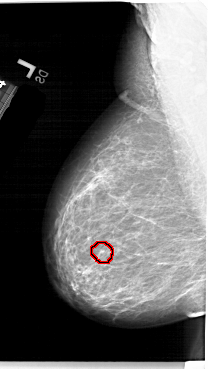

A_1235_1.LEFT_CC

FILE: A_1235_1.LEFT_CC.OVERLAY

TOTAL_ABNORMALITIES 1

ABNORMALITY 1

LESION_TYPE CALCIFICATION TYPE PLEOMORPHIC DISTRIBUTION CLUSTERED

ASSESSMENT 4

SUBTLETY 2

PATHOLOGY MALIGNANT

TOTAL_OUTLINES 1

BOUNDARY